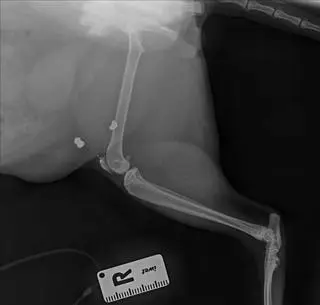

- Mój kot został postrzelony w brzuch, na szczęście ten śrut utknął tak w tym sadełku, że nic poważnego mu się nie stało. Śrut miał też koło nogi - opisuje nam pani Natalia, właścicielka czworonoga. Mieszkanka Aleksandrowa Łódzkiego dodaje, że jej pupil wychodzi tylko do pobliskich ogrodów, gdzie jest dużo przestrzeni i to tam najprawdopodobniej doszło do postrzelenia. Przyznaje, że jej kot nie jest jedynym, który został zraniony.  - Zgłosiła się do nas pani, która też ma postrzelonego kota. Sąsiedzi opowiadali, że ich kot wrócił ze złamaną szczęką, kolejny kot zaginął, zniknął z dnia na dzień. One też chodziły właśnie tam, gdzie są te ogrody - nie wierzę w zbieg okoliczności, ktoś się tutaj dobrze bawi - dodaje kobieta.

Postrzelony kot z Aleksandrowa Łódzkiego

Źródło: Katarzyna Rezler